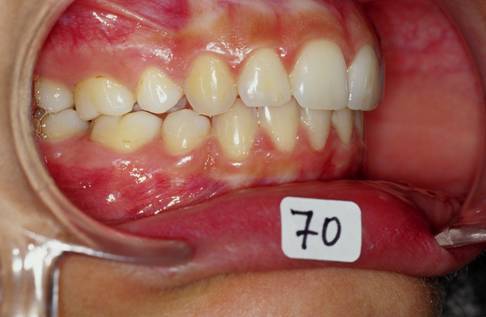

Je crois cette fois ca va marcher. Il s'agit d'une jeune fille de 12 ans, origine franco-libanaise, deja reglee depuis qqs mois. Classe II1 dentaire. Une demande majeure pour la patiente et sa maman: Les dents du haut sont trop en avant, il ne faut surtout pas les avancer ou les garder comme ca!!!

1 aswyzj - Eugenol

2 yzorem - Eugenol

3 uk1wzr - Eugenol

4 nsnllc - Eugenol

pour ce cas:

classe II squelettique(responsabilite mandibulaire),cl II dentaire,petite ddm,constriction de arc sup,flaring des incisives sup,face moyenne etroite,mesiodivergent

legere deviation des milieux

demande esthetique